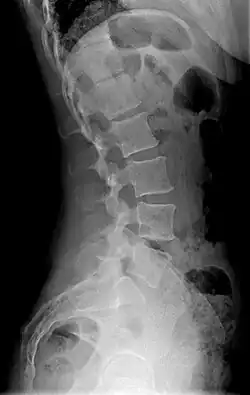

X-ray of lumbar hyperlordosis

Measurement and diagnosis of lumbar hyperlordosis can be difficult. Obliteration of vertebral end-plate landmarks by interbody fusion may make the traditional measurement of segmental lumbar lordosis more difficult. Because the L4–L5 and L5–S1 levels are most commonly involved in fusion procedures or arthrodesis and contribute to normal lumbar lordosis, it is helpful to identify a reproducible and accurate means of measuring segmental lordosis at these levels.[16][17] A visible sign of hyperlordosis is an abnormally large arch of the lower back and the person appears to be puffing out their stomach and buttocks.

Precise diagnosis is done by looking at a complete medical history, physical examination, and other tests of the patient. X-rays are used to measure the lumbar curvature. On a lateral X-ray, a normal range of the lordotic curvature of between 20° and 60° has been proposed by Stagnara et al., as measured from the inferior endplate of T12 to the inferior endplate of L5.[18] The Scoliosis Research Society has proposed a range of 40° and 60° as measured between the upper endplate of Th12 and the upper endplate of S1.[18] Individual studies, although using other reference points, have found normal ranges up to approximately 85°.[18] It is generally more pronounced in females.[18] It is relatively constant through adolescence and young adulthood, but decreases in the elderly.[18]